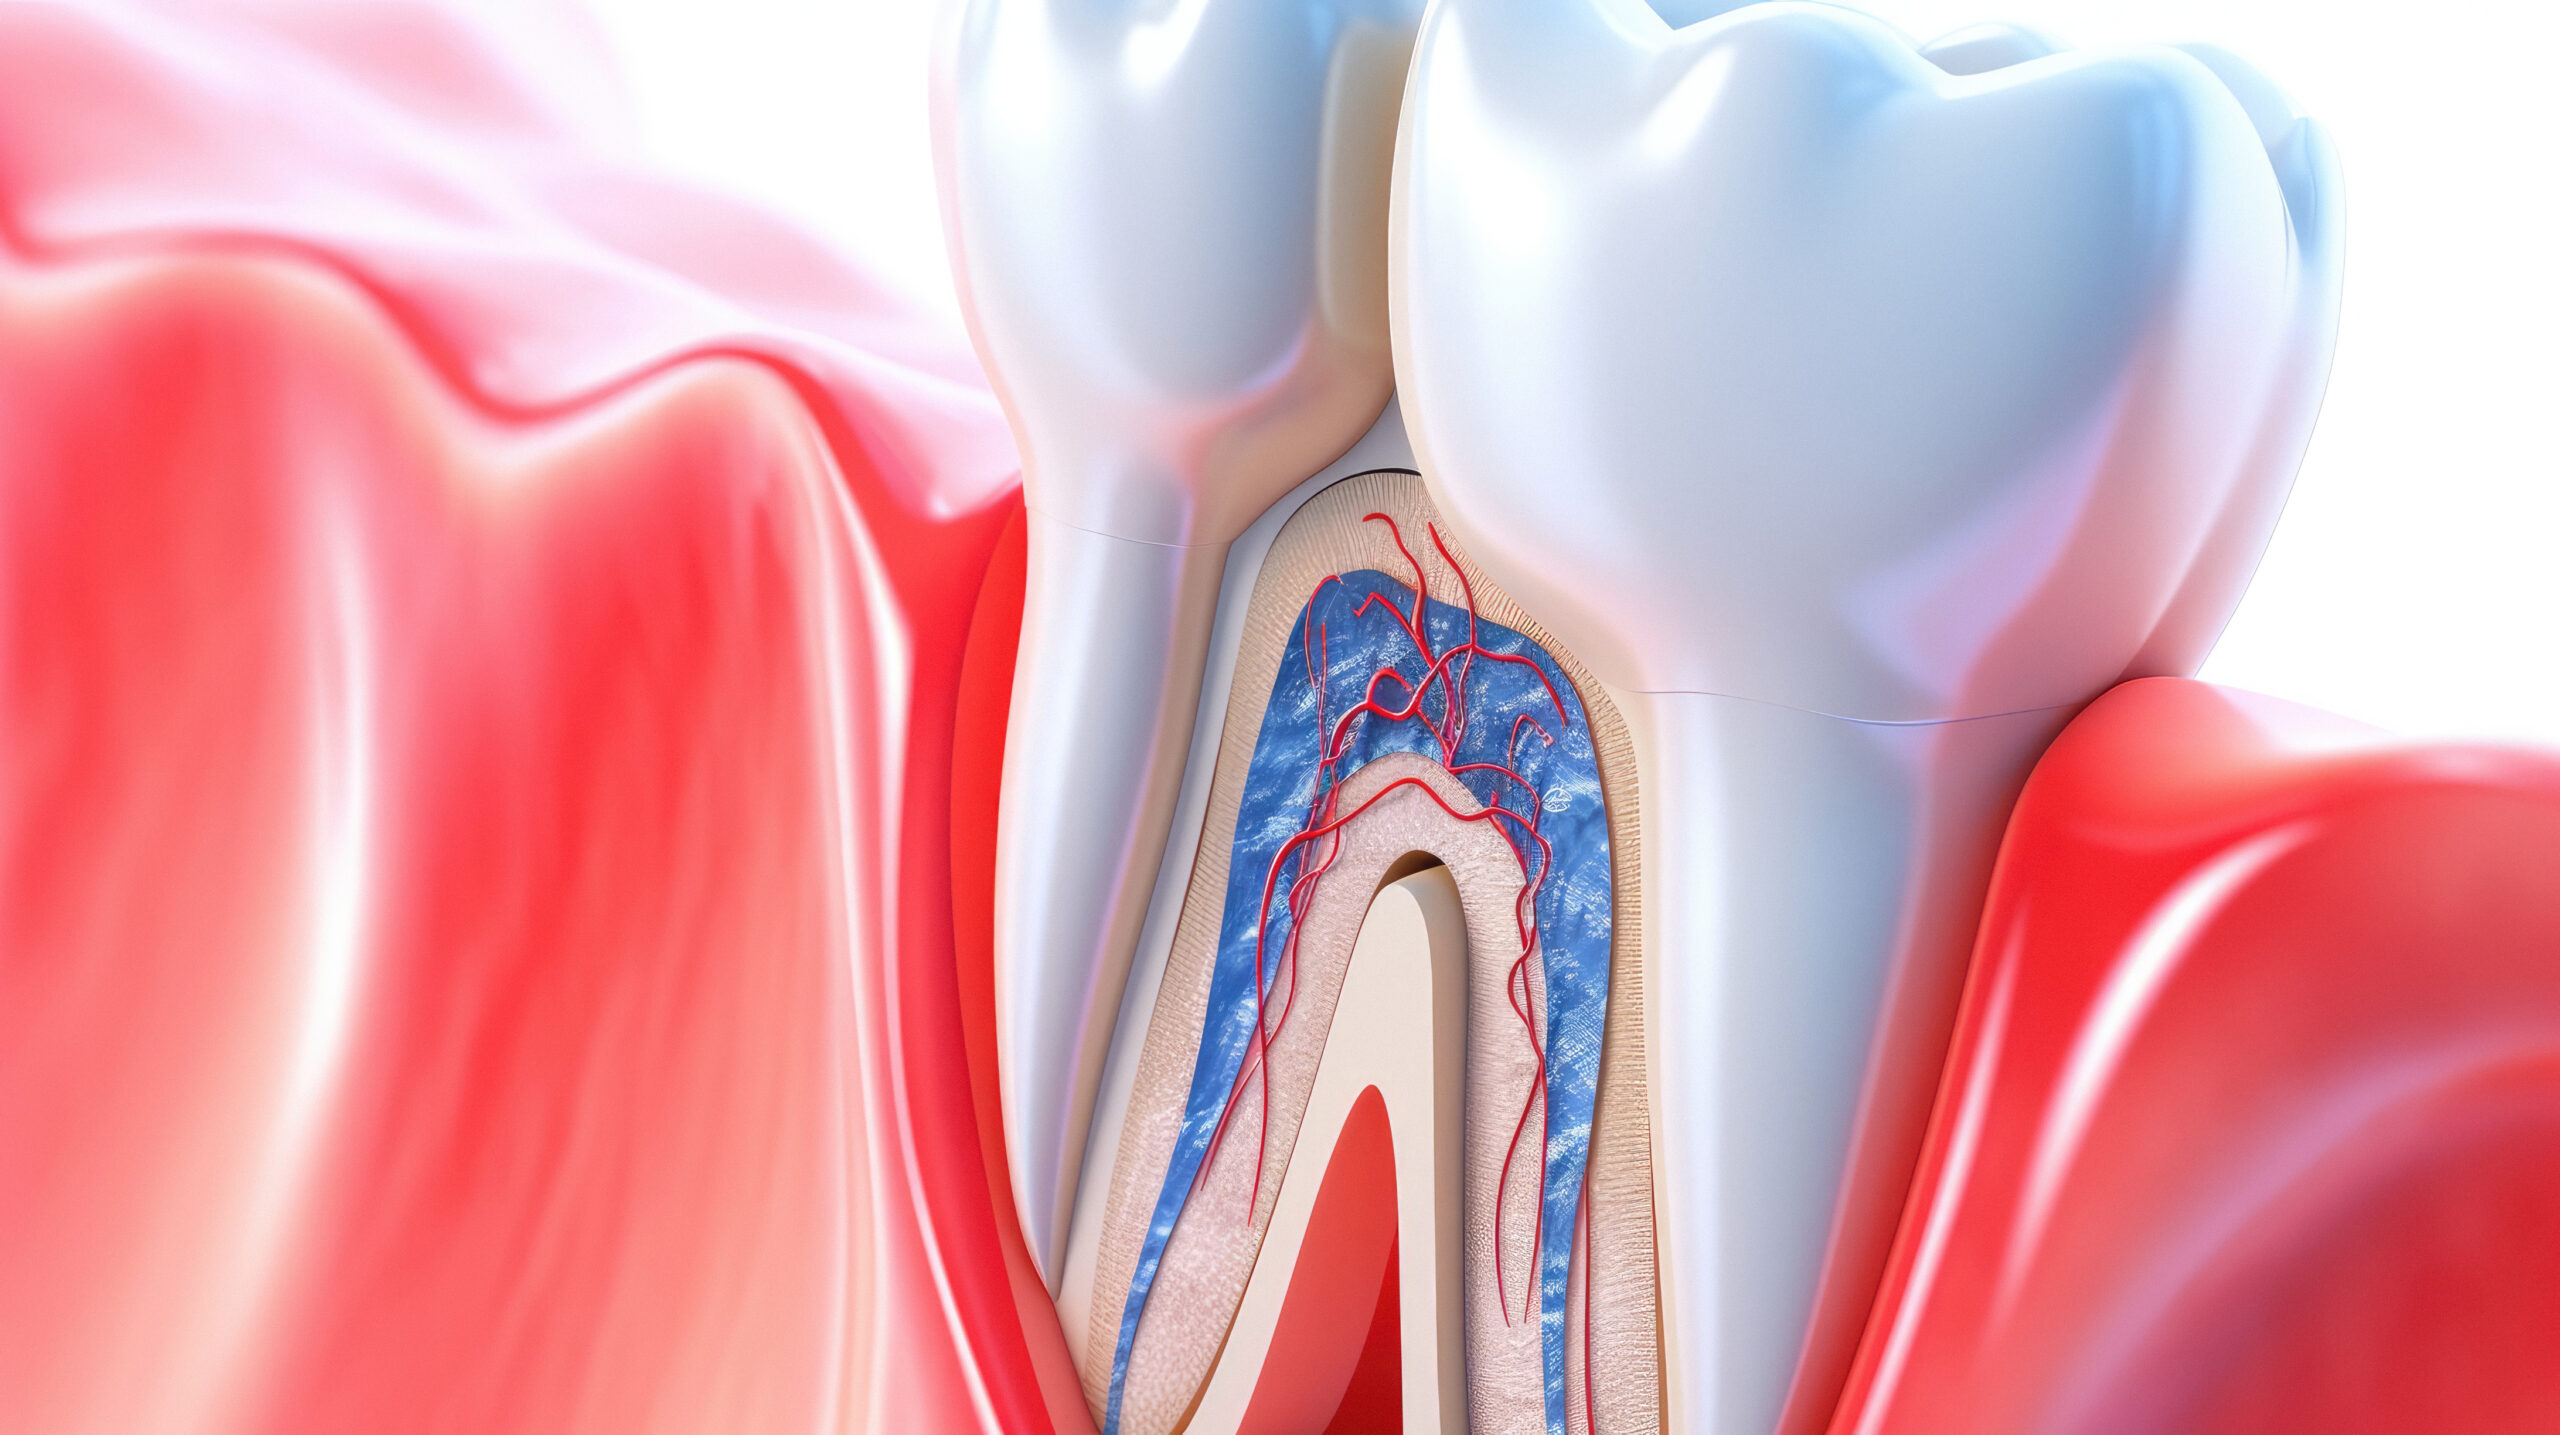

Cleaning and thoroughly disinfecting the tooth.

Removing the damaged nerve and cleaning the root canals.

Filling the canals with a special material to seal them completely.

Restoring the tooth with a filling or crown for protection.

The root canal is treated using the latest technologies and a surgical microscope.